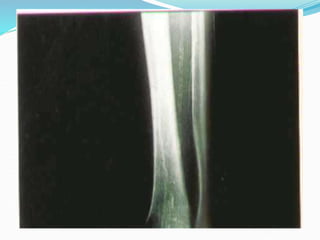

Case 3